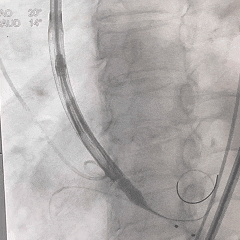

8mm外周球囊扩张髂动脉狭窄处

根部造影可见大量反流